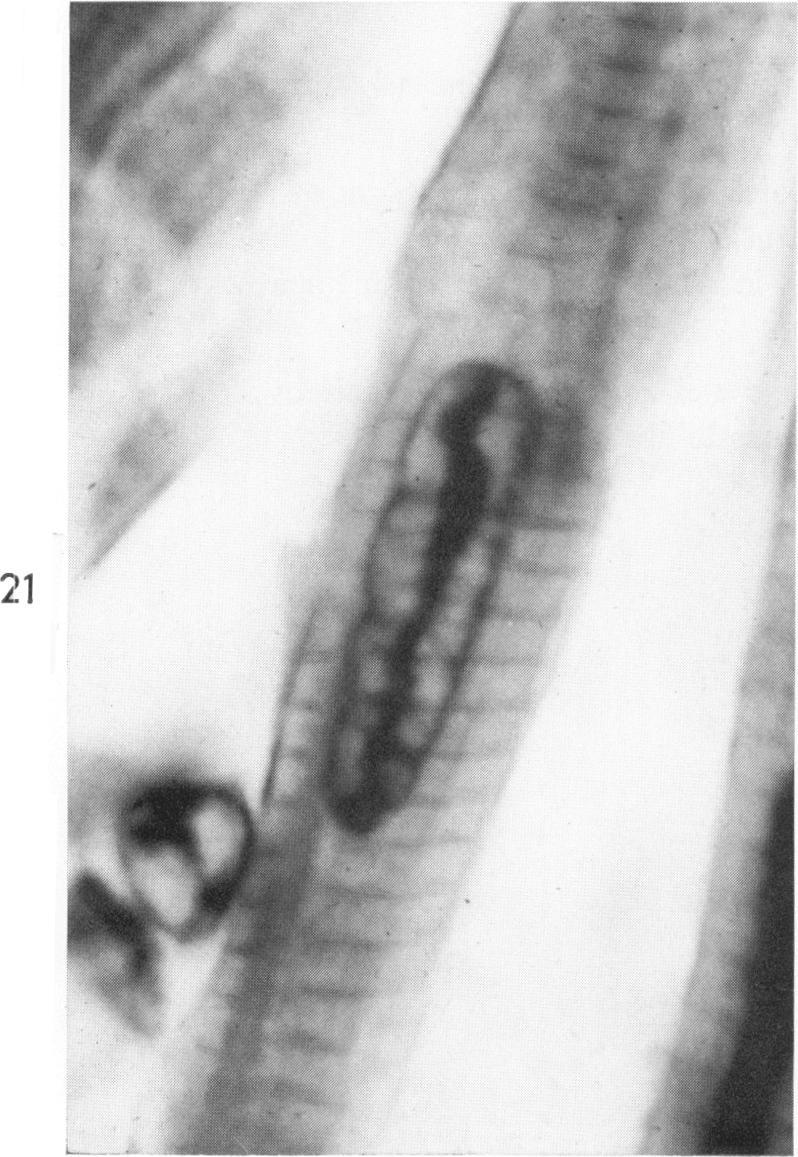

Occurrence of caterpillar nuclei within normal immature and normal appearing and altered mature heart muscle cells and the evolution of Anitschkow cells from the latter.

Am J Pathol. 1966 Jun;48(6):931-57.